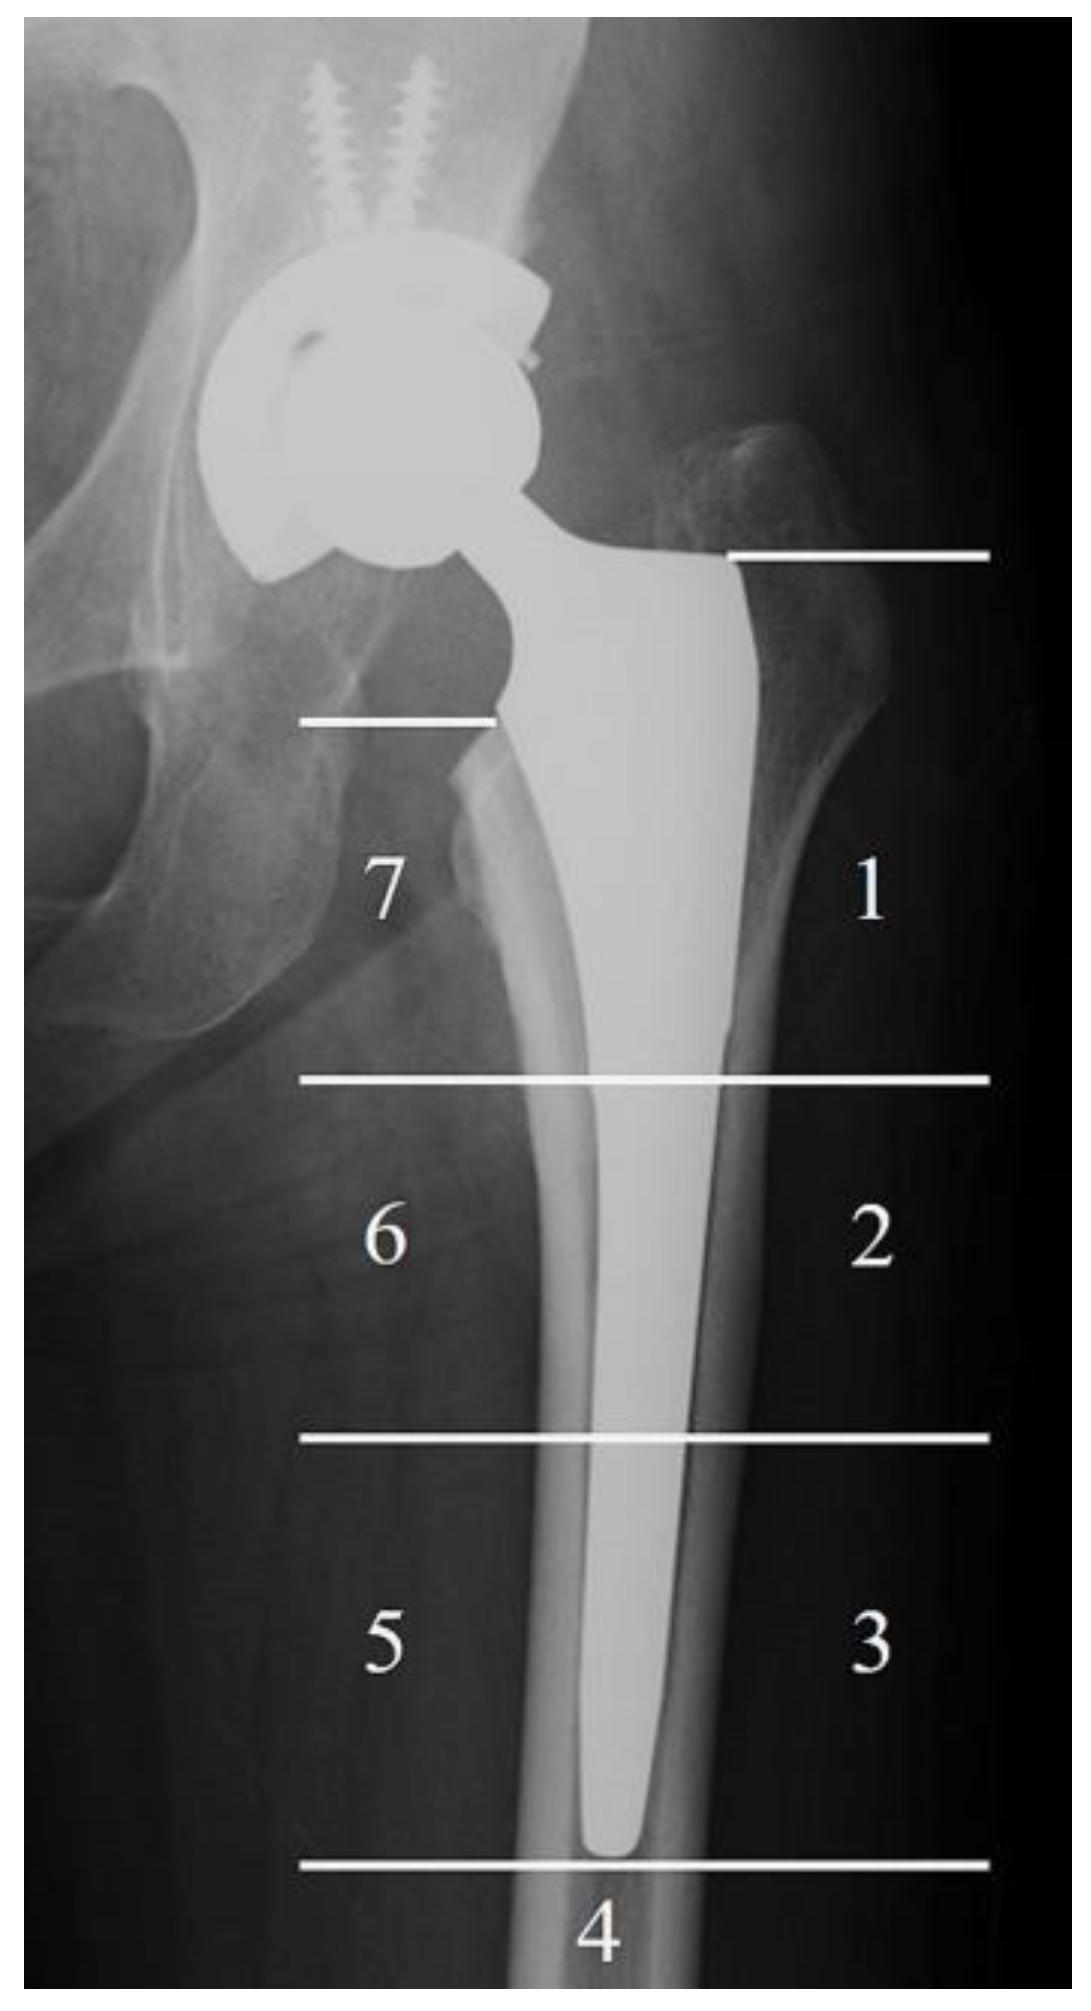

Figure 2.

The Gruen zone. The bone resorption according to stress shielding was recorded by Gruen zone. The numbers show the area of the Gruen zone.

Anteroposterior radiographs of both hips and lateral radiographs of the affected hip were obtained immediately after surgery and at the final follow-up, which was more than five years post operation, in the TNS group. In the control group, radiographs were taken immediately after surgery and at a time corresponding to the postoperative observation period of the TNS group for comparison. SS was evaluated according to a previously reported method. [14]. The incidence of SS was assessed with radiographs at the final follow-up in both groups using Engh’s classification [20]. The frequency of SS at the final follow-up was also evaluated based on the Gruen zone (Figure 2) [14,21]. Two authors (K.B. and R.K.) who did not implant the stems performed radiologic assessments of SS independently under blind conditions.

Table 3 demonstrates the incidence of SS according to the Gruen zone. The overall inter-rater agreement between Examiner 1 and Examiner 2 across all Gruen zones (Zones 1 to 7) was moderate, with a Cohen’s kappa coefficient of 0.58. This indicates a fair level of consistency in the assessment of radiographic findings between the two examiners. SS was most frequently observed in Gruen Zone 7 in both the TNS and the control groups, while approximately half of the cases showed SS in Gruen Zone 1. Zones 2, 3, and 6 were the Gruen zones in which the TNS group demonstrated a significantly lower SS frequency than the control group (p = 0.02, 0.01, and 0.001 in zone 2, 3, and 6, respectively).